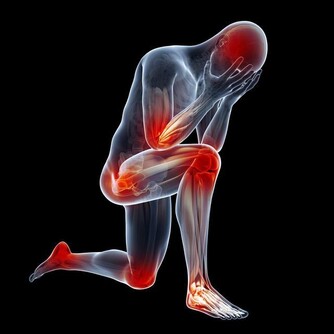

中醫提及,有心血管疾病的患者,多半有不明原因的頸部酸痛、喉嚨痛、胸痛、胃痛,甚至小指內側、靠近無名指的整條手少陰心經會麻、有緊縮感,所以問診時就會特別留意。

食指下的第二掌骨直接對應全身,從最靠近指尖的位置算起,分別對到:頭、頸、上肢、肺心、肝、胃、十二指腸、腎、腰、下腹、腿足,堪稱是人體縮小版。